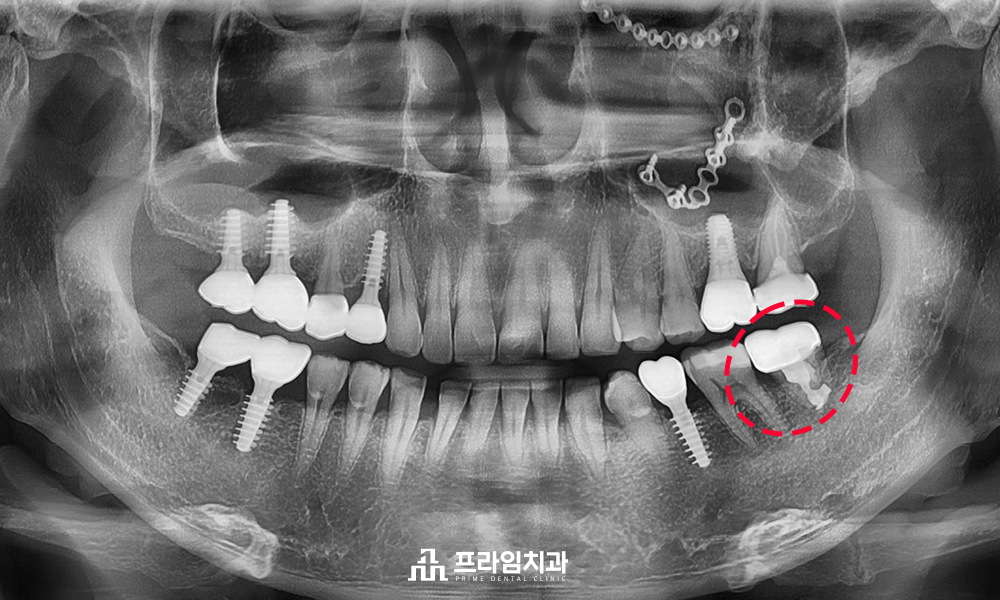

사랑니를 어금니 부위에 이식한 뒤

크라운으로 덮어 5년이 지난 후에도

문제없이 잘 사용하는 중입니다. : )

환자분께서는 하나의 영구치라도 살려

건강하게 사용할 수 있음에

긍정적인 반응을 보이셨어요.